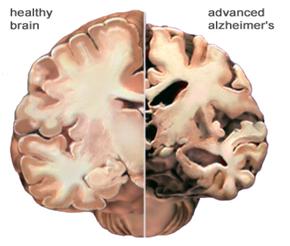

Lo studio guidato dalla UC e condotto in collaborazione con il Karolinska Institute in Svezia, afferma che il trattamento del morbo di Alzheimer potrebbe richiedere di normalizzare i livelli di una particolare proteina chiamata amiloide -beta nel cervello. Questa proteina è necessaria nella sua forma originale solubile per mantenere il cervello sano, ma a volte si indurisce in “calcoli cerebrali” o grumi, chiamati placche amiloidi.

La malattia di Alzheimer è diventata ampiamente nota come “il lungo addio” alla fine del XX secolo a causa del lento deterioramento della funzione cerebrale e della memoria. Tuttavia, più di 100 anni fa, lo scienziato Alois Alzheimer ha identificato per la prima volta le placche nel cervello dei pazienti affetti dalla malattia.

“Da allora”, afferma Espay, “gli scienziati si sono concentrati sui trattamenti per eliminare le placche. Ma il team della UC la vede diversamente: il deterioramento cognitivo potrebbe essere dovuto a un calo del peptide beta-amiloide solubile invece del corrispondente accumulo di placche amiloidi”. Per testare la loro ipotesi, i ricercatori hanno analizzato le scansioni cerebrali e il fluido spinale di 600 individui arruolati all’iniziativa di neuroimaging della malattia di Alzheimer, che avevano tutti placche amiloidi. Hanno confrontato la quantità di placche e i livelli del peptide negli individui con cognizione normale con quelli con decadimento cognitivo. Hanno scoperto che, indipendentemente dalla quantità di placche nel cervello, gli individui con alti livelli del peptide erano cognitivamente normali. Hanno anche scoperto che livelli più elevati di peptide beta-amiloide solubile erano associati a un ippocampo più grande, l’area del cervello più importante per la memoria. Secondo gli autori, con l’avanzare dell’età la maggior parte delle persone sviluppa le placche amiloidi, ma poche persone sviluppano la demenza. “Infatti, all’età di 85 anni, il 60% delle persone avrà queste placche, ma solo il 10% svilupperà la demenza”, dicono gli autori.

“La scoperta chiave della nostra analisi è che i sintomi della malattia di Alzheimer sembrano dipendere dall’esaurimento della proteina normale che è in uno stato solubile”, afferma il coautore Kariem Ezzat del Karolinska Institute. “L’approccio terapeutico futuro più rilevante per l’Alzheimer sarà il reintegro di queste proteine solubili nel cervello ai loro livelli normali“, afferma Espay.

Il team di ricerca sta ora lavorando per testare i risultati su modelli animali. In caso di successo, i trattamenti futuri potrebbero essere molto diversi da quelli provati negli ultimi due decenni. “Il trattamento”, dice Epay, “può consistere nell’aumentare la versione solubile della proteina in modo da mantenere il cervello sano, evitando che la proteina si indurisca in placche”.